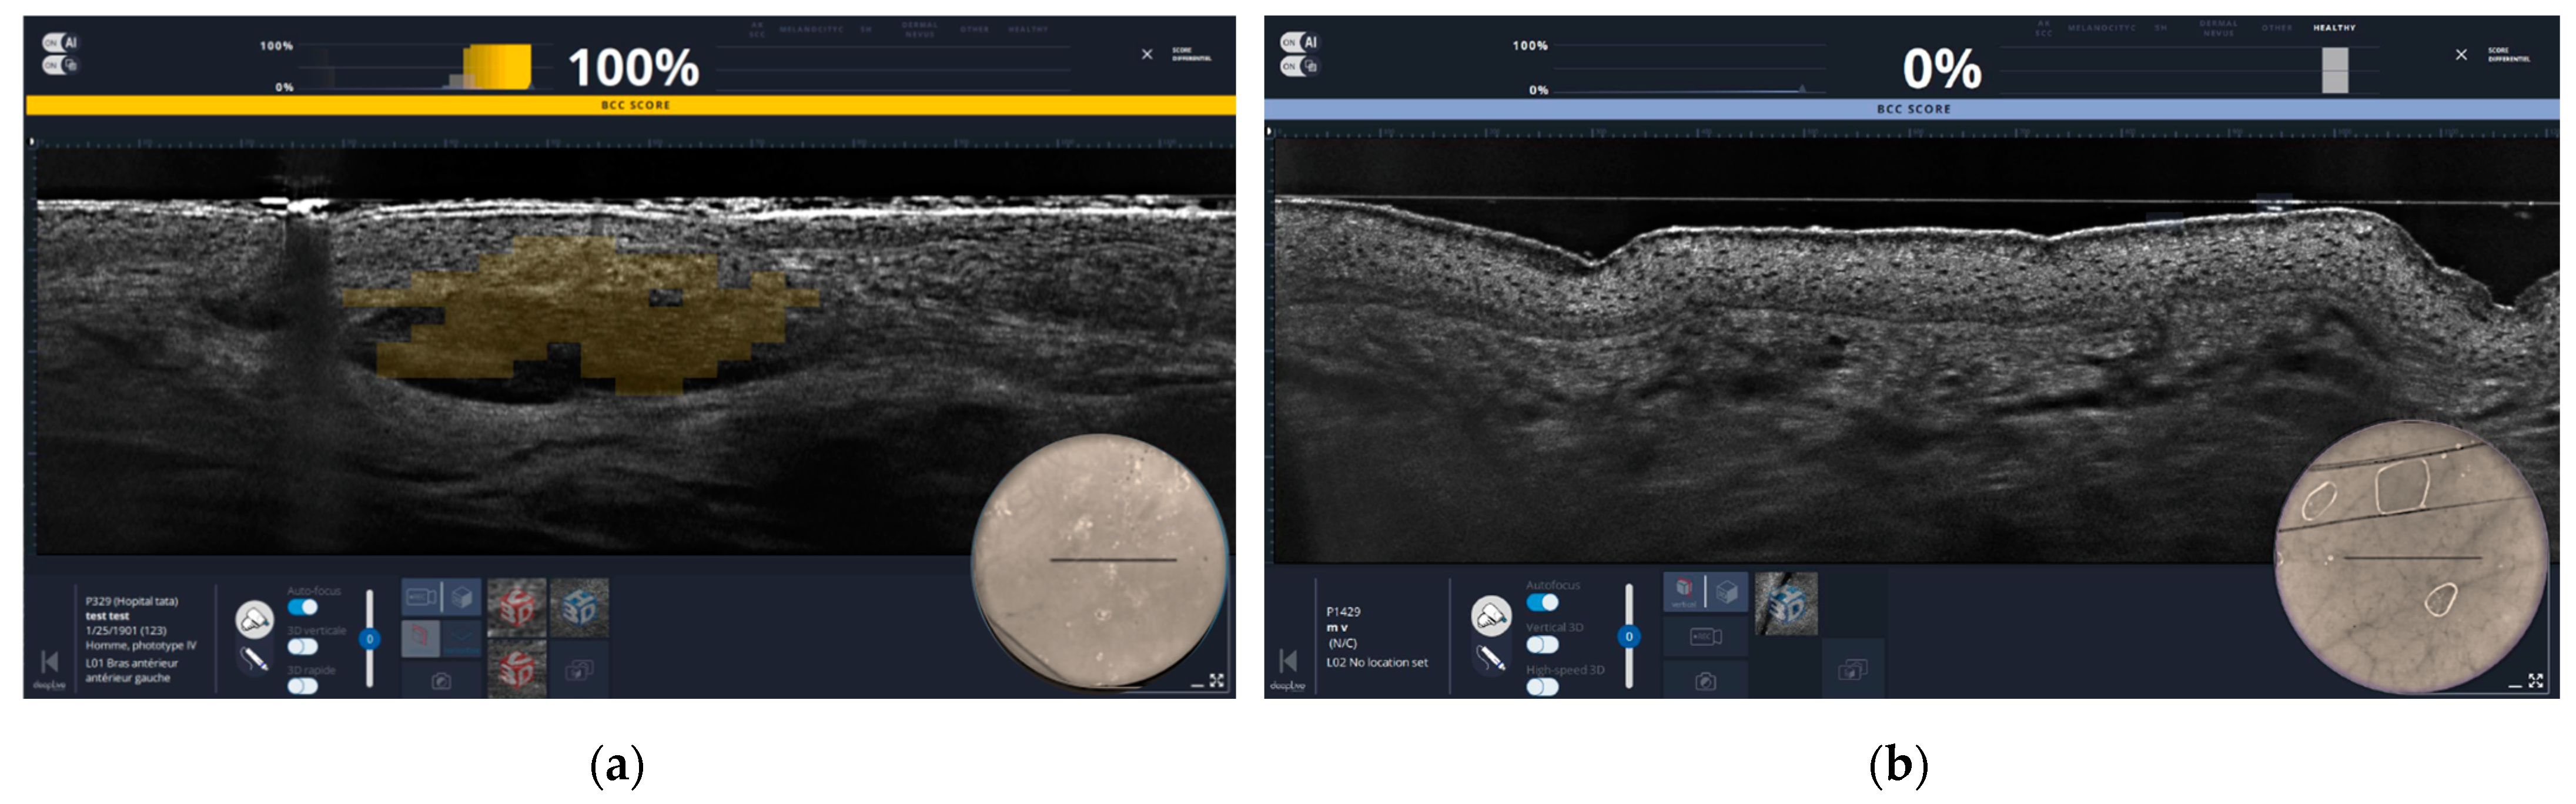

2.4. High Frequency Ultrasound (HFUS)

2.4.1. Technical Details

2.4.2. Experiences with HFUS

- In vivo

- Bozsányi, S.; Boostani, M.; Farkas, K.; Hamilton-Meikle, P.; Varga, N.N.; Szabó, B.; Vasanits, F.; Kuroli, E.; Meznerics, F.A.; Lőrincz, K.; et al. Optically Guided High-Frequency Ultrasound to Differentiate High-Risk Basal Cell Carcinoma Subtypes: A Single-Centre Prospective Study. J. Clin. Med. 2023, 12, 6910. [Google Scholar] [CrossRef] [PubMed]